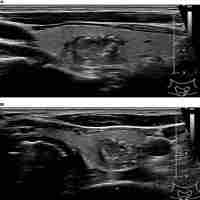

| Abstract | Our institution (University Hospital "L. Vanvitelli" - Naples, Italy) is a high-volume (HV) center in Naples metropolitan area and many patients are referred there to repeat thyroid fine-needle aspiration cytology (FNAC) after initial FNAC performed in low-volume institutions (LV). The aims of the study were to 1) examine the inter-observer agreement between HV and LV institutions according to the Italian thyroid cytology system, and 2) explore how the discordant FNAC reports were distributed in the European Thyroid Imaging and Reporting Data System (EU-TIRADS) categories. All consecutive cases of repeat FNAC performed at University Hospital "L. Vanvitelli" from January 2016 to December 2021 were retrospectively reviewed. Fleiss’ kappa (κ) was used to assess the inter-observer agreement, and categorical variables were compared by chi-square testing. P < 0.05 was considered statistically significant. A total of 124 nodules from 124 adults (mean age 49 years; mean maximum diameter 19 mm) were evaluated. Initial FNAC reports at LV were: 4 (3.2%) TIR1c, 64 (51.6%) TIR2, 48 (38.7%) TIR3A, 8 (6.5%) TIR3B, 0 TIR4, 0 TIR5. The overall FNAC reports were significantly different between the LV and HV institutions. At repeated FNAC, cytological diagnosis was unchanged in 64 (51.6%) cases including TIR2 and TIR3A results. A downgraded FNAC diagnosis (i.e., TIR2 vs TIR3A, TIR2 vs TIR3B) was observed in 36 (29%) nodules. An upgraded FNAC diagnosis (i.e., TIR3B vs TIR2, TIR3B vs TIR3A, TIR4 vs TIR3A, TIR5 vs TIR2, TIR5 vs TIR3B) was recorded in 24 (19.4%) nodules. The weighted inter-observer agreement between LV and HV institutions was poor (κ=0.133). Changed FNAC results were significantly (p=0.0023) more frequent in nodules at intermediate/high-risk (i.e., EU-TIRADS 4/5) than in those at no/low risk (EU-TIRADS 2/3) [i.e., 32/48 (66.7%) and 28/76 (36.8%), respectively]. Downgraded FNAC results were significantly more frequent in EU-TIRADS 2/3 (p=0.001) while upgraded FNAC were present only in EU-TIRADS 4/5 (24/24, 100.0%). The inter-observer agreement among LV and HV thyroid services was poor. The EU-TIRADS 4 and 5 categories included all the malignant nodules with FNAC results reclassified as higher risk (i.e., TIR3B-TIR4-TIR5) by the high-volume cytology service. |

| Subject Keyword | Neck ultrasound ICCRTC Thyroid FNAC EU-TIRADS Thyroid Nodule |